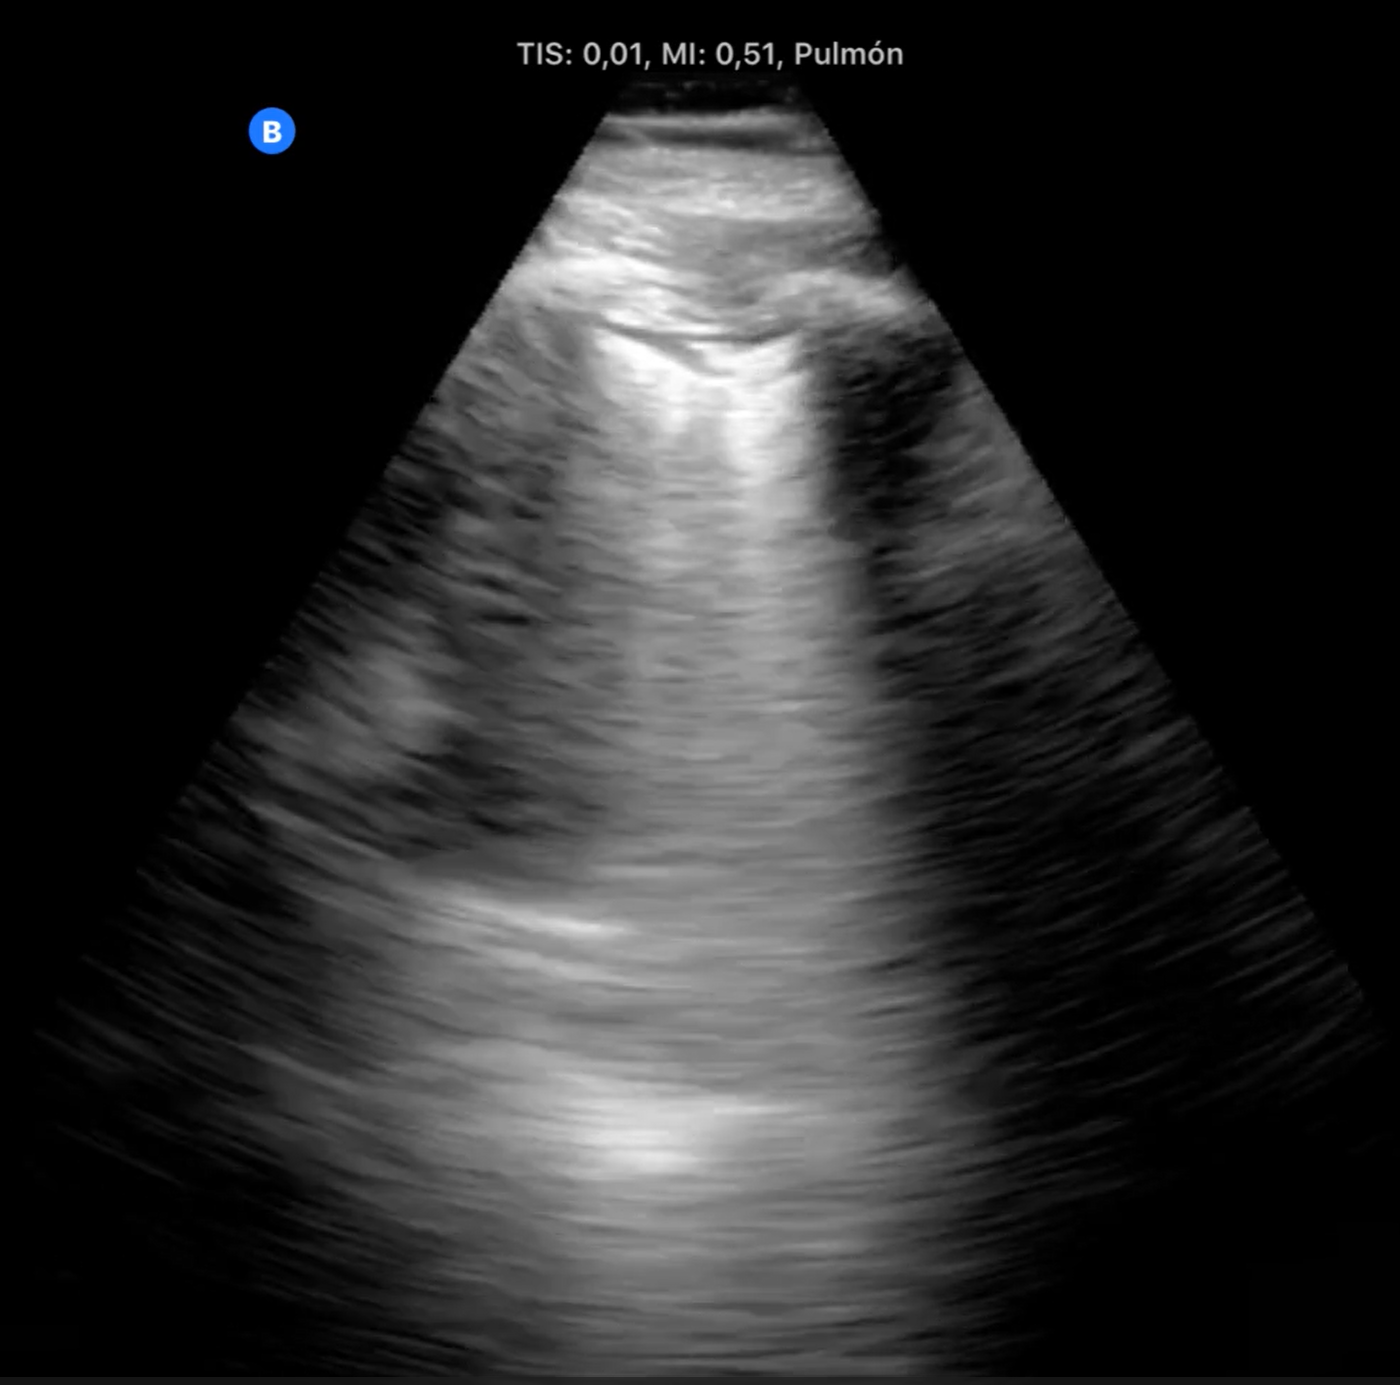

A través de una serie de casos clínicos surgidos tanto en la consulta como en los domicilios, hemos llevado a cabo una revisión de cómo aplicar la ecografía clínica para mejorar el diagnóstico diferencial del paciente con disnea y su posterior seguimiento. Tras la realización de dicha revisión bibliográfica nos reunimos los responsables de ecografía del centro de salud para realizar una serie de sesiones clínica y compartir nuestra experiencia y plantear un algoritmo sencillo de aplicar en nuestra práctica diaria.

La disnea es una sensación subjetiva de dificultad para respirar siendo común a múltiples situaciones clínicas de elevada prevalencia. Las causas más frecuentes, las de origen respiratorio y las de causa cardiaca, incluso comparten factores de riesgo, por lo que en ocasiones coinciden en el mismo paciente. En estas circunstancias no resulta sencillo solo por la clínica intuir cual puede ser el origen de la disnea. La ecografía multiórgano, constituye una herramienta muy útil para determinar o descartar el origen cardiaco de la disnea. Siendo imprescindible en los pacientes inmovilizados, en los que los ecógrafos ultraportables nos ha aportado un nuevo manejo de la disnea en el paciente domiciliario.

La ecografía multiórgano junto con la mejora de la portabilidad de los ecógrafos nos permiten hacer un diagnóstico más certero del paciente que consulta por disnea tanto en el centro de salud como en su domicilio.